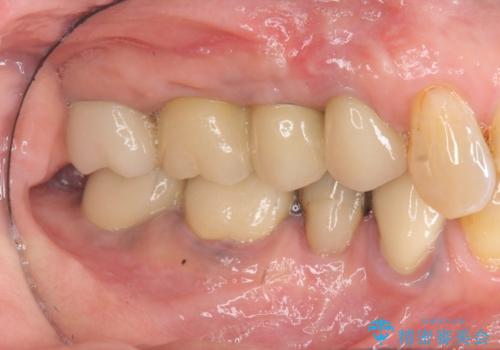

インプラント治療が終了し、しっかりと咬合機能が回復しまた食事が楽しめるようになりました。